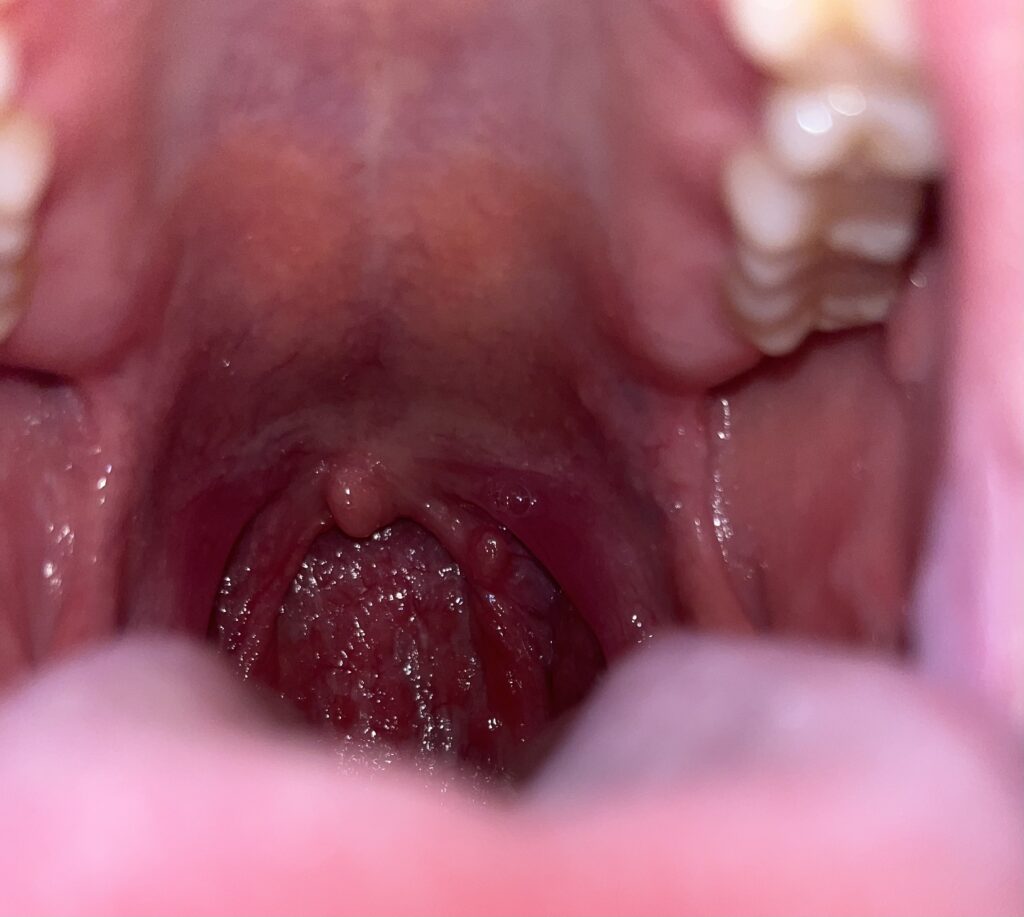

「自律神経が整う」には、12対の脳神経が健常に働く事が必要ですが、その中でも大きな因子となる"舌咽神経"

(※舌の後ろ1/3、喉の奥や口蓋垂(のどちんこ)を支配する神経)

自律神経由来の不調があると、口を開いて鏡を覗いて見た時に、舌が盛り上がって口蓋垂が見えなかったり、口蓋垂が左右のどちらかに曲がっていると言ったサインがあります。

(※口蓋垂が曲がっていると、曲がっていない側の腹側迷走神経が麻痺している可能性あり)